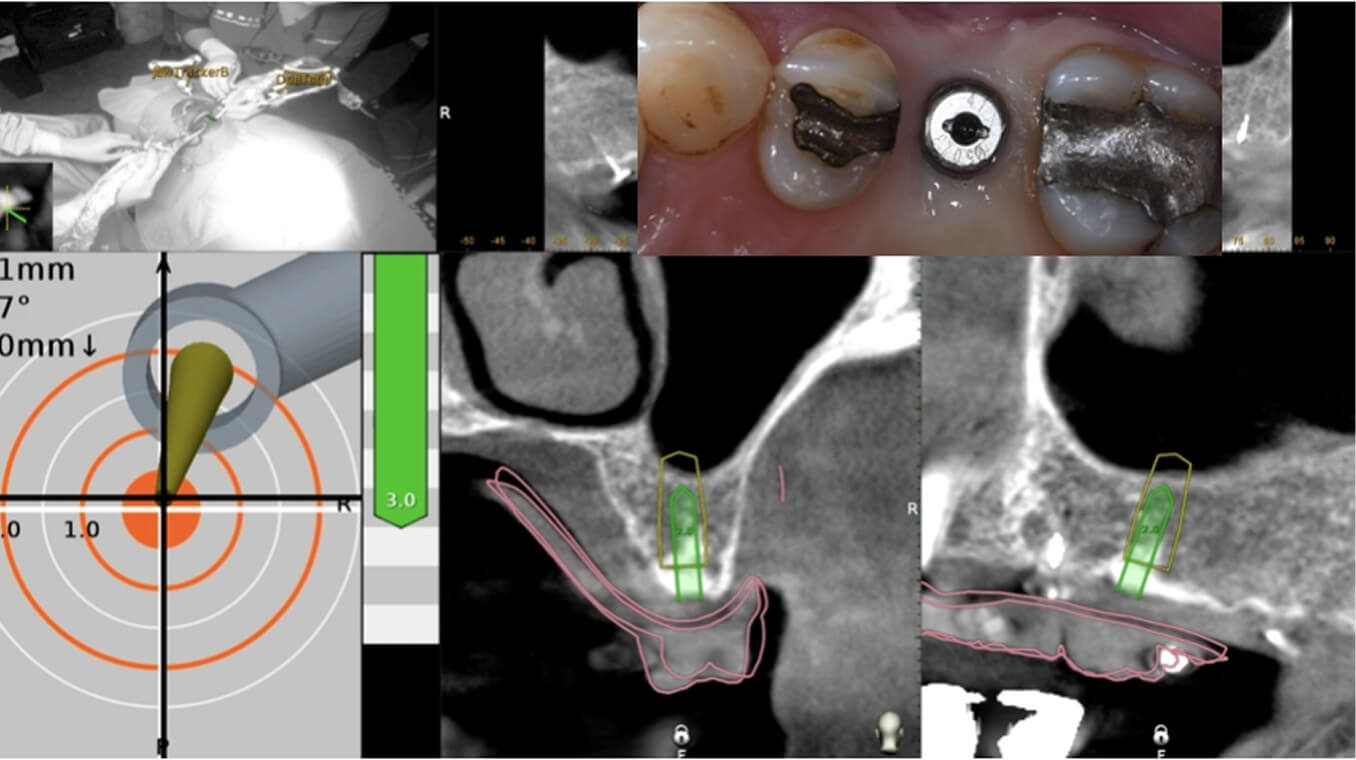

- Navident即時導航植牙系統,讓手術更精準、更安全,降低風險、縮短時間,帶來安心舒適的治療體驗

數位植牙的好處? 不管採取何種植牙治療方式,「4D微創導航系統」牙科技術能夠輔助醫師,在治療時,除了能透過醫師臨床的經驗與技術外,更能精準的控制與判斷病患的所有狀況,降低療程時可能發生的風險,以及減緩術後的不適感。 醫師會在病人的缺牙上,裝上一顆如同「監視器」的機器,搭配「4D動態導航系統」牙科技術,讓醫師在植牙的時候,能夠即時、精準的監測病人口腔骨頭內的狀況。 植牙有黃金治療時間嗎? 植牙的黃金治療期是「越來越快好!」為什麼是「越快越好呢?」最主要是因為牙齒與牙槽骨是相互依存的關係,當缺牙的第一年,骨頭會吸收得特別快,接下來每年以等比的速度吸收。 當口腔內的牙齒,有任何問題或是已經出現缺牙的情況,應該盡快尋求牙醫師的協助!進行治療與骨頭重建的需求評估,已避免增加重建的困難度,甚至無法治療。 到底適合「植牙」,還是要做利用兩邊牙齒做「牙橋」,最終還是需要經過醫師的專業判斷。 如何在茫茫醫海中,尋找適合的植牙醫師? 「一般牙科、贋復補綴科、口腔顎面外科、牙周專科」現代人很喜歡上網做功課,但想要找植牙醫師時,卻不知道從何尋找到適合的植牙醫師。 其實,能夠提供患者專業植牙技術的醫師,通常會受過「贋復補綴科、口腔顎面外科、牙周病科」這3大科的專業訓練。 擔心花錢後植牙出現問題又無法處理,如果長期看診的牙醫診所沒有相關的專業醫師,可以請醫師幫忙轉介。 另外,也可以挑選幾位自己喜歡的醫師,進行面診諮詢,找出最適合的醫師。最後,與醫師充分的溝通、配合也是植牙成功與否的重要關鍵。 植牙的步驟 植牙的流程大致可以分為幾個階段:資料蒐集、資料分析與重建理想牙位、植牙手術與植牙臨時假牙製作,以及最後最重要的植牙假牙製作。 植牙諮詢的第一步「資料蒐集」 資料蒐集、分析: 先利用口腔掃描機、臉部掃描儀、X光片、斷層掃描等,蒐集病患口腔整體環境、牙齦、骨頭的臨床資訊,以及紀錄顳顎關節與咬合的情況。 植牙手術 植牙手術:在經過專業的醫療團隊,進行術前評估後,以及擬定個人化的治療方針後,就會進入植牙手術的步驟,手術的步驟,會先進行牙齦翻瓣、鑽孔、植入人工牙根、縫合、拆線等。 不少人聽到上述步驟,或許已經頭皮發麻,專業的醫療團隊在治療的過程中,會搭配「舒眠麻醉」治療,能夠降低病患在過程中的不適感與恐聚感。 而通常人工牙根的癒合期大約需要6-12週的癒合,待癒合後才會進入「植牙臨時假牙製作」的製作。 植牙永久有效? 植牙有保固期 ? 「植牙成功後,就一勞永逸了嗎?就不用與醫師相見了嗎?」植牙它是鈦金屬釘子,植入骨頭癒合後,它不會蛀牙。但是,植牙周圍的牙肉跟骨頭,如果不妥善保養的話,還是會導致牙周病的發生,就是所謂的植體周圍炎。 植牙上方接出的牙冠,就好比買一台車,牙冠用久了,就如同車子用久了,零件、螺絲依舊會出現損毀的狀況,所以定期的回診保養追蹤是相當重要的。 通常植牙牙套完成後,至少半年回診一次,讓牙醫師檢查確認植牙附近牙齒沒有累積牙箘斑牙結石、植體周圍牙肉沒有發炎化膿,中間固定的螺絲沒有鬆動、牙套沒有破損、咬合狀況穩定等。 此外,患者必須維持良好的口腔清潔,可以參照之前我介紹的牙齒清潔方式,來保持好的口腔衛生、少抽菸等,如此搭配定期的回診檢查,可延長植體壽命。 植體的構造 植牙的治療過程很漫長,很多病患最常問的是「嘴巴內裝上的到底是什麼東西?」 今天的「植牙芯教室」就要帶你來認識「植牙整體的構造」(Dental implant) 口腔內的植牙由上→下依序是:牙冠、支台體、植體。 牙冠:又稱假牙冠、牙套,它是提供如同真牙的咀嚼功能,並且恢復美觀,永久性的牙冠最常見的材質為:全瓷、金屬合金、瓷熔合金屬。 支台齒:連接牙冠與植體的延伸部分,在中間點扮演重要角色,因為它必須要支撐牙冠的咬力,同時又要提供牙肉健康的生長環境,所以專科醫師在安裝時,必須依造病患口腔的狀況「客製化」的設計,ˊ尋找最適合的形狀、大小與角度。 植體:置入於缺牙的牙槽骨中,功能是取代原有的「牙根」,負責穩固牙齒的地基,目前最常見的植體材質為純鈦、鈦合金。 植牙x牙冠材質 對於越來越講求美觀的現代人來說,花錢植牙,當然希望它能美觀性與功能性兼具。 今天的「植牙芯教室」就要帶你來認識「牙冠材質」 目前,市面上永久性的牙冠最常見的材質為全瓷、金屬合金、瓷融合金屬 。 1.全瓷牙冠:材料有氧化鋯、強化玻璃瓷,不需要使用金屬,材質與人體的生物相容性高,同時具備高硬度的特性、高耐磨、耐高溫。在外觀上,呈色自然如同真牙,美觀性極佳。 2.瓷融合金屬牙冠:由於合金的成分複雜,若是高貴金屬的成分(黃金、白金)不夠高時,在口腔高溫潮溼的環境下,金屬容易腐蝕,導致表面粗糙,使牙菌斑難以徹底清潔,就容易造成牙齦發炎,並且染色,長期在美觀上、實用性都難以符合,對於外觀講求自然的病患。 3.金屬合金牙冠:由於整體採用金屬製作,所以不容易破裂、折斷,但是外觀呈現金屬色,所以當張開口時,便能夠一眼看出假牙的位置,如果使用金屬和金的牙冠,建議使用高貴金屬成分較高的材質。 植牙前的注意事項 想要提高植牙治療成功率,醫師與病患互相配合很重要,從術前的資料蒐集、評估與診斷,依據病人的情況,給予專屬的治療方針,從術中的治療過程,到術後的維護都非常重要,先來談談植牙前要注意那些事情。 1.保持口腔衛生:口腔清潔是植牙成功的最大關鍵 2.降低煙癮:抽菸會影響植牙的成功率,應該要盡量避免,如果能夠戒菸成功,更能提高植牙的成功率。 3.持續服用慢性病藥物:如果有在服用慢性病(高血壓、糖尿病等),在術前的諮詢,務必完整提供用藥歷史給醫師。 植牙後的潔牙步驟-工具篇 「植牙疏於潔牙與保健,百萬台幣立刻船過水無痕。」這是血淋淋的案例,真的不要以為,植牙完成後就一勞永逸。 術後的口腔清潔與維護非常重要!非常重要!非常重要!因為植牙的「使用壽命」,有非常大的關聯性。 植牙維護有三寶:牙刷、牙間刷、牙線 牙刷:可以選擇自己習慣的刷頭,或者選擇刷頭短小、刷毛軟硬適中的牙刷 牙間刷:當牙齦萎縮、牙縫變大時,應該選擇適合牙縫大小的牙間刷,用來清潔齒間的縫隙、牙套底層的牙菌斑與食物殘渣。 牙線:使用超級牙線,來清潔牙橋下的支柱牙部分。 漱口水、沖牙機等,這些只是輔助工具,千萬不能把它當作正規的潔牙器材。 植牙後的潔牙步驟-清潔篇 植牙的清潔方式。 首先:使用牙刷在假牙與牙肉的交界,採用刷牙法,來回輕刷至少10次。 接著:使用牙間刷,輕貼牙齒的表面,進行前後清洗,按照同一個方式,從舌側進入,輕貼牙齒表面,再做一次清潔,每次動作至少5次。 最後:使用大約45CM的牙線,可以使用穿引器的輔助,深入牙橋底下做清潔,每次動作至少5次。 植牙後的潔牙步驟-電動牙刷VS.一般牙刷 「做完牙套後可以用電動牙刷刷牙嗎?潔牙工具怎麼選?」上一篇,談了植牙的清潔方式,究竟植牙到底該不該用電動牙刷?答案是「可以」。 科學研究指出,使用電動牙刷,能更深入清潔到牙縫與牙齒倒凹處,尤其對於手部協調性沒那麼高的人,以及牙齒排列凌亂者,在清潔上能夠達到更好的效果。 刷頭的選擇:一樣要以刷頭小、刷毛軟硬度適中的刷頭,建議每1-3個月,或者外觀出現彎曲變形,刷頭就必須更換。千萬不要因為刷頭,比一般牙刷貴捨不得更換,反而會讓潔牙效果打折扣。 潔牙方式:電動牙刷與一般牙刷的潔牙方式的差異在於,電動牙刷只需要將刷頭輕放在單顆牙齒上,讓刷頭在牙齒與牙肉的交界處轉動,手不需要來回移動刷頭。但是千萬不要重壓,施壓過多的力道在牙齒上,反而對於牙齦是種傷害。 另外,不管使用電動牙刷或一般牙刷,都一定要使用牙線、牙間刷,來清潔牙齒與牙齒間的鄰接面,確保牙菌斑被清除。 潔牙時間:三餐飯後,30分鐘內如果能夠潔牙是最好的,如果無法達到,睡前徹底的潔牙是最重要!另外,潔牙時一定要有耐性,不要為了節省時間,隨便刷2.3下就結束。 如何選擇:預算、操作與攜帶方便度為首要考量,而且選擇具有「經濟部標準檢驗局」檢驗合格的產品,設計不良的電動牙刷,可能會造成口腔受傷。 植牙後的術後照護 植牙的最終成功與否,術後照顧真的非常重要!務必遵從醫囑,以下是照護的重點。 1.冰敷:術後1周,依舊會有些許的腫脹與輕微的瘀青,在48小時內,建議患者可以冰敷,在臉頰外側冰敷15-20分鐘,休息10分鐘,重覆動作到48小時。 2.不要泡溫泉、熱水澡,以及從事游泳與劇烈的運動。 3.飲食方面:初期還是會建議以流質、軟度高的食物為主,過燙、過冰的流質食物則不宜,應該避免食用過燙、辛辣、含有酒精成分刺激性的食物。 4.降低菸癮:為了讓植牙的傷口能順利恢復,醫學上皆有文獻記載,術後1周必須降低菸癮。 5.定期回診:植牙完成還是必須定期回診,讓醫師確認傷口、口腔健康的情形。 根據手術療程的不同,每一項術後的照護方式也有所差異,未來會跟大家分享與討論。 植牙後就能一勞永逸,不會有牙周病? 大多數的病患都知道,植牙前要先把牙周病及其他口內問題處理好,以降低口內細菌數量,才能夠進行植牙,但是很多病患以為,植牙成功,同時也能跟牙周病永久說再見,這觀念完全不正確。 簡單說「牙周病」是牙齒的周圍骨頭受到細菌的破壞,所造成的結果。因此,在植牙後,如果植體周遭的牙肉與骨頭,沒有得到妥善的清潔與照顧,還是會造成口腔內細菌的滋生,一樣會導致牙周病的發生。 植牙後,是不是也跟敏感性牙齒Say Bye Bye 一般所說的「敏感性牙齒」真正的學名是「牙本質知覺敏感症(Dentin Hypersensitivity)」會造成敏感性牙齒,主要原因是在於牙齒外層的琺瑯質被磨耗後,失去保護的功能; 或是牙齦萎縮牙根裸露時,都會造成牙本質內的神經小管暴露,當受到冷熱、吹氣、和壓力等刺激下,所產生的神經疼痛不適感。 植牙後,重建的人工牙冠內沒有神經,所以不會有敏感性牙齒的發生。然而,其他的自然牙齒,不會因為植牙而受到改變,當琺瑯質被破壞時,依舊會造成牙齒敏感性的問題。 骨質疏鬆的人適合植牙嗎? 「骨質疏鬆」有越來越年輕化的趨勢,除了因為年齡的增長之外,身體未獲得適當的保養也是元兇之一。如果是輕微的骨質疏鬆,只要適當的補充鈣質,想要植牙依舊沒有問題!整體還是必須交由專業醫師評估。 「骨鬆患者」,尤其是有在服用高劑量或施打抗蝕骨作用的藥物,是會影響植牙的成功率。原因在於,大多數的抗骨質疏鬆藥物,含有雙磷酸鹽,會影響骨骼細胞修補的功能,讓顎骨無法修復。所以如果有服用相關藥物,植牙前一定要告知醫師。 我是高血壓患者,能夠植牙嗎? 在高血壓控制好的前提下,是可以進行植牙手術的!正常的血壓是指收縮壓120/舒張壓80mmHg,當血壓偏高時,會增加手術中的出血狀況,提升手術的複雜度,甚至會提高手術後的感染率。 很多高血壓患者會服用「抗凝血藥物」。「抗凝血藥物」可能會在手術時,出現傷口流血不止的問題,所以醫師在進行植牙評估時,一定要讓醫師了解自身的慢性病史與用藥,並且盡可能尋找能提供詳細治療計畫,以及擅長微創植牙手術的醫師,降低植牙的風險。 我是糖尿病患者,能夠植牙嗎? 糖尿病患者與高血壓患者,都是在控制良好的前提下,能夠完成植牙手術。由於糖尿病控制不良的患者,細胞修復的能力與免疫系統,跟正常人比起來比較低,相對的牙周組織再生能力、傷口癒合情況也比較差。 所以想要植牙,必須同時與新陳代謝科醫師與植牙醫師相互合作,穩定血糖。除此之外,糖尿病患者也應該養成良好的口腔保健習慣,在經過醫師的專業評估,提供完善的治療計畫。 糖尿病與牙周病的關係? 「牙周病已經被列為糖尿病的併發症之一」前面談到「只要控制好血糖」依舊能夠植牙。我們也提到植牙前,一定要把牙周病控制住。今天我們就來談談「牙周病與糖尿病控制不良的關係」。 事實上,糖尿控制不良的病患發生牙周病的機率是正常人的3倍。最主要的原因,口腔細菌量會比正常人多,由於免疫系統比較差,更容易受到感染,所以傷口的復原能力也較低。 一旦糖尿病控制不良者得到牙周病時,病程也會跟著加速,骨頭被破壞與受損的速度也會加快。並且,因為身體長期發炎,將會導致血糖更不易控制。 癌症患者適合植牙嗎? 「癌症已經連續多年佔據國人10死因的首位」而癌症到底能不能進行植牙手術呢?首先,醫師會先了解病人的癌症種類與期數,以及過去的病史、治療史、用藥史,經由病人提供的資料,來做精準的判斷。 癌症的放射治療、免疫抑制等是會影響到傷口的癒合,治療上會使用到,抗骨吸收藥物 (antiresorptive agents)與抗血管生成藥物(antiangiogenic agent)等,都很有可能增加顎骨壞死的風險。另外,頭頸部經過放射線照射後,也會造成骨細胞的活性降低。 而且病人在接受化療、標靶藥物時,也會因為治療後,免疫力降低,細胞修復能力變弱,如果在治療期間,或是在治療後,想要做植牙,都應該先找醫師進行評估身體各項數值,以提高植牙成功率。 懷孕期間能夠植牙嗎? 雖然植牙是一個小手術,但是通常醫師都不會建議準媽咪們,在這時候進行植牙手術,首先,因為植牙是必須照X光檢查,在懷孕期間,應盡量避免暴露在輻射線下。 同時植牙必須經過麻醉的步驟,雖然麻藥會經由尿液排除體外,但大多數麻藥都含有「血管收縮劑」的成分,在治療過程中引發的加倍焦慮,可能會造成者子宮提前收縮的風險。所以會建議想植牙的準媽咪,產後再進行植牙手術。 產後、哺乳期植牙注意事項 「醫師,我正在哺乳期能植牙嗎?」在懷孕期間,就算已經完成第一階段的植牙手術,醫師為了保護母體與胎兒,會直接將療程暫停至產後,但是女性「產後要多久才能植牙?」、「哺乳期能植牙嗎?」成為許多媽媽最常問的問題。 事實上,女性產後的身體狀況恢復到一定的程度,就能夠進行植牙。而為了擔心麻醉藥或是抗生素、止痛藥分泌到母乳,加上每種藥物的半衰期不同,通常會建議,服用完最後一次藥物,在相隔24小時後,才進行哺乳。 服用健康食品是否會影響植牙 「維他命C、B群、魚油、銀杏、補鈣產品...」各式各樣的保健食品有吃有安心,很多病患到了診間,最常問我的問題之一「醫師,我有在服用各類的保健食品,會影響植牙嗎?」 事實上,需要看服用保健食品萃取的成分而定,不是所有的保養品食品,都會影響植牙的。如果營養品中含有「抗凝血作用」成分的保健食品,例如:銀杏、紅花。會建議在術前1周暫停服用。 雖然,適當的服用保健食品,確實有益於健康,但是在進行植牙評估時,還是務必告知,讓醫師做更正確的評估。 植牙要局部麻醉還是全身麻醉? 「植牙到底要全身麻醉,還是局部麻醉?麻醉的方式有哪些?差異性、有沒有後遺症?」許多病患都會有相同的疑問,從今天開始,一連串的文章來解惑。 其實,植牙手術跟一般口腔治療的方式一樣,能夠在病患清醒情況下進行治療,醫師通常會使用局部麻醉藥內含少比例血管收縮劑(Epinephrine),針對病人的手術內容,與治療所需的時間,給予準確的麻醉劑量。 由於大部分的局部麻醉藥,含有血管收縮劑,之前文章有提到高血壓的患者,必須在做治療諮詢時,提供用藥史與血壓控制情形,並且在手術當天,都應該接受血壓的測量,已確定用藥的安全性。 植牙的成功率?植牙失敗怎麼解?植牙的後遺症? 「植牙能100%成功嗎?植牙後是不是就再也不用回診?當植牙開始出現問題時,怎麼辦?植牙失敗後該如何治療?」這些問題是現在病患在選擇植牙時,很重要的考量。 「植牙成功率及植體壽命的長短」其實,最重要的是取決於醫師、病患有沒有合作無間,醫師與病患都應該在治療的過程中,扮演好彼此的角色,才能在植體成功骨整合後,延長使用的壽命。 病人,在諮詢時,要確實的將藥物史、病史提供給醫師。在治療期間,遵照醫囑、落實口腔衛生,並且在術後定期回診。此外,當植體出現任何情況時,必須立刻尋求醫師的協助「及早發現、及早治療」。 醫師,在技術、經驗上必須給予病患精準個人化的治療方針,並且選用大品牌的植體、生物醫材,提高治療成功率。同時,隨時吸收醫療新知,並將它運用,讓病患得到最好的治療。 上述都是植牙成功不可或缺的關鍵之一。 植牙後出狀況x牙冠瓷破裂 「植牙後出狀況怎麼辦?」 就如同之前所說,植牙就像是一部車子,用久了零件會出現受損的情況,要聊「出狀況怎麼辦?」就要回歸問題的根源來對症下藥,接下來,我將針對「植牙後常見的幾大狀況」來做詳細的說明: 牙冠瓷破裂:可將假牙取下,送修補瓷以回復美觀及咬合功能。因為牙科材料學的進步,新式二氧化鋯牙冠 (Zirconia),幾乎不會有破裂的狀況,這也是目前牙冠材質中,在品質與美觀上的表現,都擁有較高的穩定性。專業的贋復醫師在修復之前,會先把連接體跟牙冠中間的隙縫清潔乾淨,讓植體免於細菌感染的風險。 植牙後出狀況x植體配件的鬆脫、受損 「植體配件的鬆脫、受損」,之前的植牙芯教室,我們有介紹,牙冠與支台齒內含有各種不同的小零件,當植體用久了,零件開始出現狀況,該如何處理? 要談到該如何處置之前,要先了解,為什麼會發生「植體配件的鬆脫、受損」的狀況,大致可以把原因歸類為:零件壽命、植體長期咬合受力。 病患完成植牙後,在每半年的定期回診,牙醫師都會針對這些細部零件做確認,確定是否有鬆脫或晃動的情形出現。 一旦出現螺絲的鬆脫情況,沒有及時治療,螺絲就會斷裂在植體內,而要從植體內,將斷裂的螺絲取出,是件複雜又具高風險的療程,必須由經過專業訓練的植牙贋復科醫師來做處置,在往後的文章,將再做更詳細的說明。 植牙的麻醉方式有哪些? 「舒眠麻醉、全身麻醉、笑氣麻醉」這是目前大家在搜尋資料時,比較容尋找到的關鍵字,今天就來簡單介紹,這些麻醉的專有名詞。 舒眠麻醉:目前贋復科醫師最常使用的麻醉方式,屬於淺層麻醉,能夠讓病患在放鬆的情況下進行治療,也能夠降低局部麻醉的用藥量,關於「舒眠麻醉」接下來會一系列的介紹。 全身麻醉:屬於深度麻醉,麻醉藥的劑量會讓病患意識消失,而且無法自主呼吸,術後的恢復期較長,必須要在開刀房內進行。 笑氣麻醉:主要是用來鎮靜,而非麻醉,有些病患在做口內局部麻醉時,依舊會感受到看牙的緊張感,因此,有些醫院或診所,會備有笑氣設備,幫助病患在局部麻醉時,能夠鎮定。 植牙的評估要件懶人包 Q:缺牙會影響到那些層面? A:身體、心理都會受到影響,長期缺牙會讓導致「咬合障礙」 Q:到底要植牙,還是要做假牙? A:需要經過醫師的專業評估與判斷,「假牙」與「植牙」各有優、缺點。 Q:幾歲適合植牙? A:只要經過牙醫師臨床的評估,不管是25歲較年輕的缺牙病患,或者80歲的族群都能。 Q:如何在茫茫醫海中,尋找適合的植牙醫師? A:專業植牙技術的醫師通常會受過「贋復補綴科、口腔顎面外科、牙周病科」3大科的專業訓練。 Q:怕痛的人,如何進行植牙手術? A:現在也出現了「舒眠治療」,讓患者在治療上,大幅減低焦慮感。 Q:我是高血壓患者能植牙嗎? A:在高血壓控制好的前提下,是可以進行植牙手術的! Q:骨質疏鬆的人適合植牙嗎? A:如果是輕微的骨質疏鬆,只要適當的補充鈣質,想要植牙依舊沒有問題。 Q:癌症患者適合植牙嗎? A:在癌症治療期間或是在治療後,想要做植牙,都應該先找醫師進行評估身體各項數值,以提高植牙成功率。 Q:懷孕期間能夠植牙嗎? A:植牙必須經過麻醉的步驟,所以想植牙的準媽咪,產後再進行植牙手術。 Q:服用健康食品是否會影響植牙? A:需要看服用保健食品萃取的成分而定,不是所有的保養品食品,都會影響植牙的 舒眠治療懶人包 Q:舒眠治療有健保給付嗎? A:舒眠自療跟植牙如同屬於自費項目,並無健保給付。 Q:舒眠治療前需要做哪一些準備? A:由於治療藥物的濃度,與個人身體狀況與病史有關,所以患者必須確實告訴醫師用藥的習慣以及病史,必要時,在舒眠治療前,醫師會要求病患,先做身體健康檢查。 Q:平常有習慣吃保健食品需要暫停嗎? A:大部分的保健食品都不需要停藥。 Q:舒眠治療需要禁食嗎? A:需要的,必須至少禁食6-8小時,如果是在上午進行,前晚12時之後就不可飲食,如果是下午,則是早餐過後,就不能進食。 Q:舒眠治療前的禁食,若有需要服用藥物該怎麼辦? A:禁食期間,服用少量的水吃藥是被允許的。 Q:有服用抗凝血藥物怎麼辦? A:通常不需要停藥,除非是經過專業醫師指示,才需要停藥。 Q:舒眠治療當天可以駕駛嗎? A:舒眠完成後,可能會有頭暈的狀況出現,建議在親朋好友陪同下,搭乘交通工具前往診所。 Q:舒眠治療後的注意事項? A:在完成治療後,患者應休息20-30分鐘,確保沒有暈眩、嗜睡的情況發生,才能離開診所。 植體品牌 ║史得勞曼(Straumann)║ 瑞士的植牙品牌,經過許多臨床醫學研究證實,是植體品牌中邊緣骨流失最少的系統之一,其特殊植體連接體的設計,使牙冠與植體緊密結合,增加假牙的穩定度,降低鬆脫、晃動的機率。 →https://reurl.cc/8lDo1X ║諾保科(Nobel biocare)║ 瑞典的植牙品牌,在2008年推出的NobelActive系統,植體特殊的螺紋設計及表面處理,適用於骨質條件狀況比較複雜的患者。 →https://reurl.cc/xDN9zL ║亞仕特(Astra Tech Implant)║ 瑞典的植牙品牌,在植體與連結面的設計上,採用特殊的圓錐六角形內接式的設計,穩定的接口,能降低牙冠與支台齒,鬆脫的情形。 →https://reurl.cc/jd91bn ║百好(BIOHORIZONS)║ 來自美國的植體品牌,BioHorizons採用硬度、生物性較高的鈦合金材質,同時擁有特殊的Laser-lok專利技術,不僅能降低植體牙周病的發生機率,又達到兼顧美觀的功能。 →https://reurl.cc/YlYvZn ║貝格莎曼杜(BEGO Semados)║ 德國在地生根、製造生產超過125年的歷史悠久,植體表面特殊的TiPure技術,能夠幫助植體與齒槽骨結合,達到最大的整合功能,同時,也能幫助植體壽命的延長。 →https://reurl.cc/oD81ov” - 植牙後的保養 2026.01.19